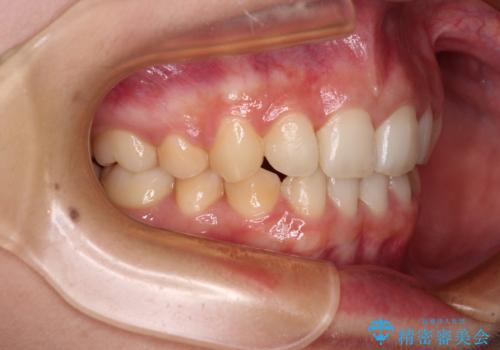

通常の抜歯矯正と抜くべき歯の位置が異なるため、咬みにくさが残ってしまうのではないかと懸念されましたが、咬み合わせに違和感なく、スムーズに治療を終えることができました。

- 治療期間

- 1年8ヶ月